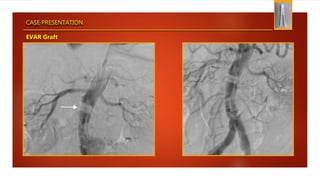

CASE PRESENTATION

EVAR Graft